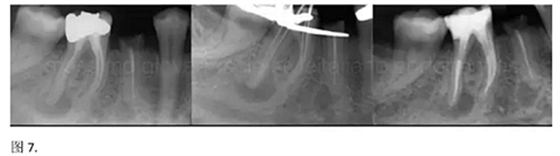

開髓后預(yù)敞、探查根管、建立直線通路是根管機(jī)械預(yù)備的第一步。在這些階段中,醫(yī)生可能會經(jīng)常遇到一些困難。這些難題包括器械折斷、臺階形成、根管歧坡或根管拉直、帶狀穿孔、根尖穿孔、根尖肘形、根尖堵塞。所有這些錯誤可導(dǎo)致根管系統(tǒng)清潔不完善從而降低牙髓治療成功率。